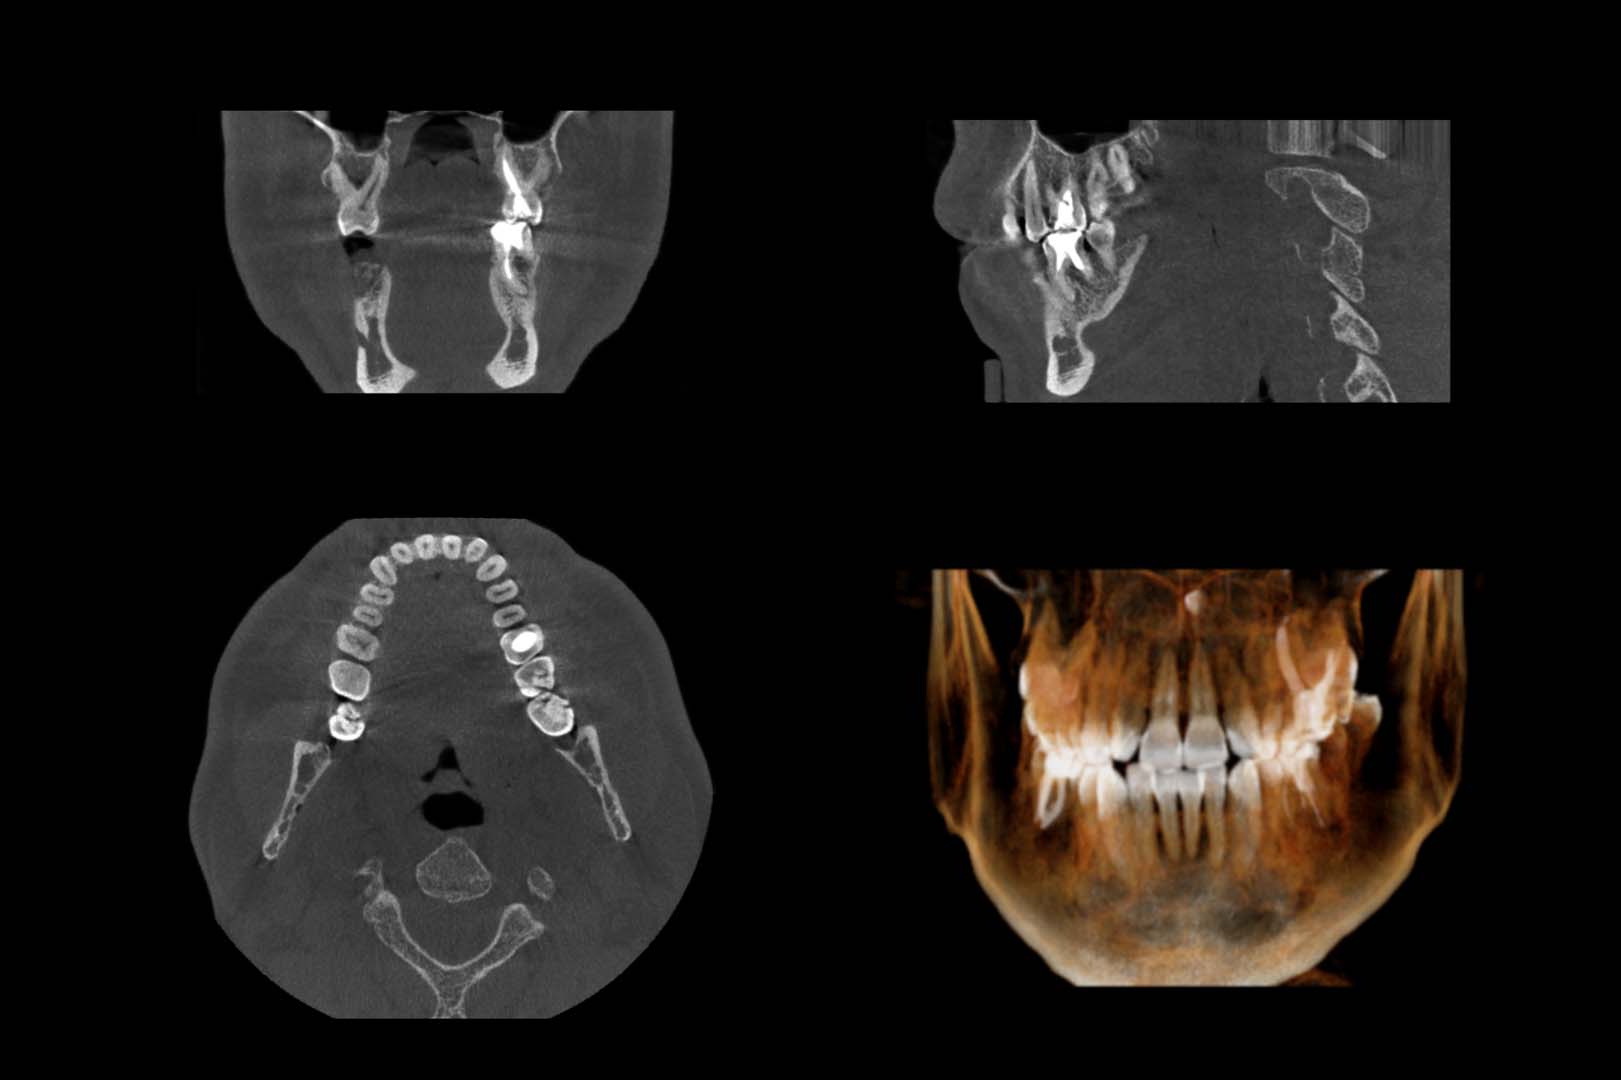

A cone beam CT scan involves a special type of x-ray that allows us to see the details of your oral and facial health. This scan is more than just a typical x-ray, since it allows us to identify nerve pathways, soft tissue and bone before providing you with treatment. This gives us a clear view of your oral health so that treatment is easier and more effective for you. The scan takes just seconds in our office and provides us with a highly detailed image.

Most often, you'll need a CT scan be fore you have oral surgery performed in our office. This is because the CT scan allows us to identify soft tissues, bone and even nerves that could come into play when performing a surgical procedure. You might even need to have this scan done if you come to us with an emergency or when we are trying to find a problem that you're experiencing. The amount of radiation used to produce an image using the CT scan machine is minimal and considered safe and beneficial for most patients.